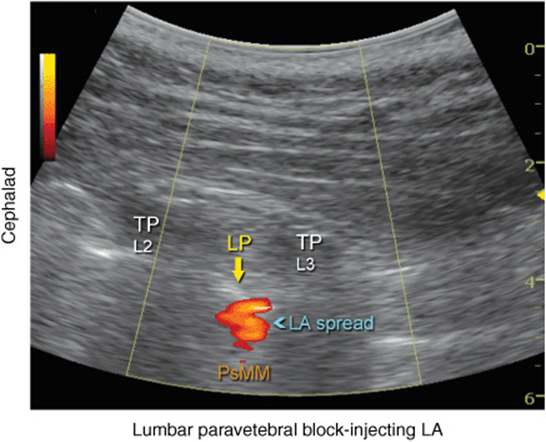

More recently, Karmakar and colleagues described the “trident sign technique,” which uses an easily recognizable ultrasonographic landmark, transverse processes, and an out-of-plane needle insertion. The trident sign technique derives its name from the characteristic ultrasonographic appearance of the transverse processes (trident) to estimate the depth and location of the lumbar plexus. After application of ultrasound gel to the skin over the lumbar paravertebral region, the ultrasound transducer is positioned approximately 3 to 4 cm lateral and parallel to the lumbar spine to produce a longitudinal scan of the lumbar paravertebral region (Figure 46-7). Then the transducer is moved caudally, while still maintaining the same orientation, until the sacrum and the L5 transverse process become visible (Figure 46-8). The lumbar transverse processes are identified by their hyperechoic reflections and acoustic shadowing beneath which is typical of bone. Once the L5 transverse process is visible, the transducer is moved cephalad gradually, to identify the L3-L4 level. The goal of the technique is to guide the needle through the acoustic window between the transverse processes (between the “teeth of the trident”) of L3-L4 or L2-L3 into the posterior part of the psoas major muscle containing the roots of the lumbar plexus (Figure 46-2B). After obtaining ipsilateral quadriceps muscle contractions, the block is carried out using the previously described injection and pharmacology considerations (Figures 46-9 and 46-10).

FIGURE 46-10. Local anesthetic (LA) disposition during injection of local anesthetic into the psoas muscle and the L2-L3 level. The spread of LA is often not well seen using two-dimensional imaging. LP, lumbar plexus; TP, transverse process.